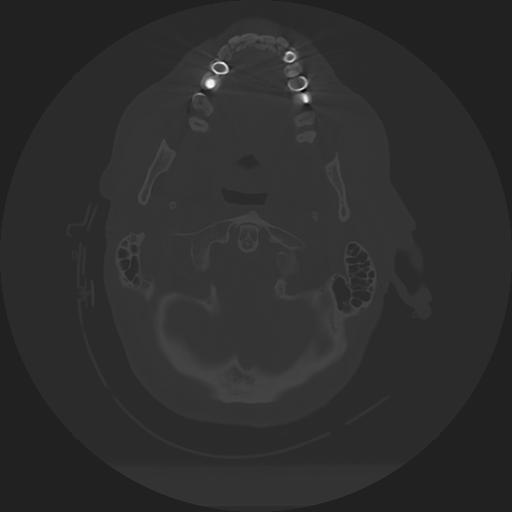

11 HUESO,,Axial,2.0,HUESO,,